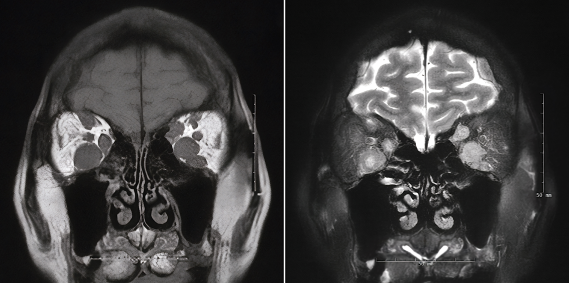

Metastatic EOM lesions are more commonly unilateral with bilateral involvement seen in approximately one-third of patients..[1] The most commonly involved muscles are the lateral rectus and medical rectus. Lesions are rarely seen in the oblique muscles, and no cases have been reported of isolated oblique muscle lesions without involvement of at least one rectus muscle.[1][4] Imaging usually reveals isolated enlargement of affected muscles, but it may also demonstrate nodular lesions.[1][7] In unclear cases, fine-needle aspiration biopsy may be performed, although this is not required for diagnosis.[8] Histopathologic characteristics will differ in EOM metastases depending on the primary tumor. In some cases, the histologic features of orbital metastasis may differ from those of the primary tumor.[7]

EOM metastasis may not be apparent on initial ocular examination. The diagnosis is suggested by clinical history and confirmed with imaging, which may include computed tomography, magnetic resonance imaging, or ultrasound.[8]

CT or MRI of the orbits are the most frequently used diagnostic imaging studies. Although less commonly used, ultrasound (A-scan or B-scan) has been equally successful in detecting lesions.[1] A minority of patients undergo biopsy for confirmation of the diagnosis, but fine needle aspiration may be performed after imaging is obtained.